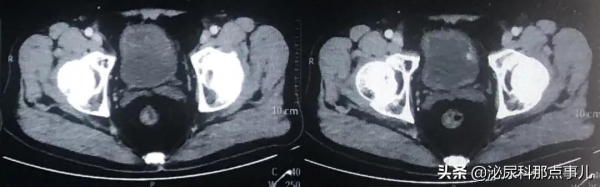

術前盆腔CT:

2021.08-2021.10行3週期維迪西妥單抗(2.5mg/kg,2w)聯合特瑞普利單抗(3mg/kg, 2w)新輔助治療後,此時再次透過的影像學檢查評估,發現原可疑轉移淋巴結消失,患者無不適感覺,再行1週期維迪西妥單抗聯合特瑞普利單抗新輔助治療後,患者經1個月休息準備充分後,擬實施手術治療。